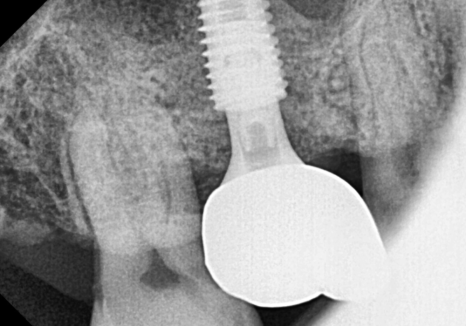

임플란트를 식립했습니다.

240831

그리고 뼈와 임플란트가

한 몸처럼 단단히 굳을 때까지

5개월을 묵묵히 기다린 뒤에야,

튼튼한 새 치아를 만들어 드릴 수 있었습니다.

상일역 치과, 오래된 금니 빠짐 241207